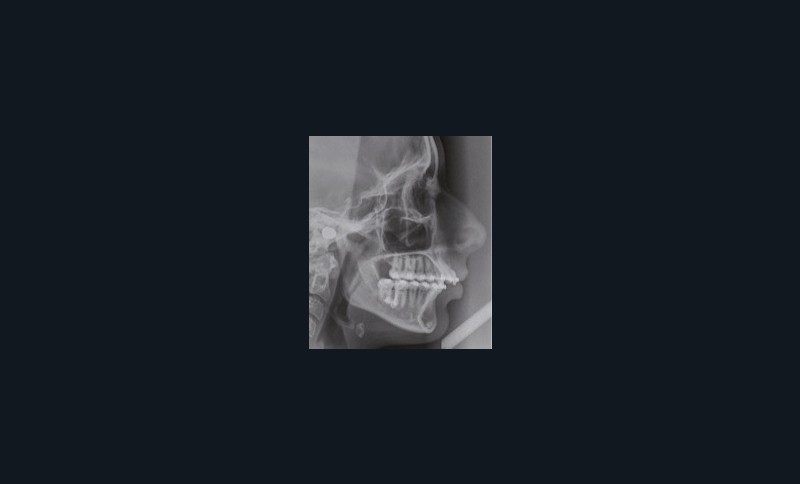

Son visage de face est équilibré et symétrique ; en revanche, au niveau de son profil elle présente une rétromandibulie avec un sillon labio-mentonnier marqué.

À la vue de l’examen radiographique, elle est au stade CS6 d’après la méthode de maturation vertébrale de Baccetti [1]. Elle présente une classe II squelettique de Ballard par rétrognathie mandibulaire avec un ANB de 9° et un AoBo de 9 mm sur un schéma facial normo-divergent. L’incisive mandibulaire est vestibulo-versée (IMPA = 114°). Le maxillaire est bien positionné. Elle présente de plus une dysharmonie dento-dentaire (DDD) antérieure par excès mandibulaire.

Nous avons pu repositionner l’incisive mandibulaire de 8° (fig. 10), obtenir un surplomb correspondant à la classe II d’Angle et ainsi réaliser l’avancée mandibulaire. Le chirurgien accompagne celle-ci d’une génioplastie afin d’harmoniser le profil. Nous corrigeons la DDD par stripping des incisives mandibulaires ce qui permet de corriger encore de 1° l’axe incisif.

À propos du cas, on note la persistance d’une petite classe II squelettique (ANB = 5°). Cependant, l’axe de l’incisive maxillaire ne permet pas une correction plus importante de la classe II par avancée mandibulaire car le surplomb est déjà faible et l’incisive maxillaire est légèrement versée (106°). Les axes de 11 et 12 auraient pu être améliorés.